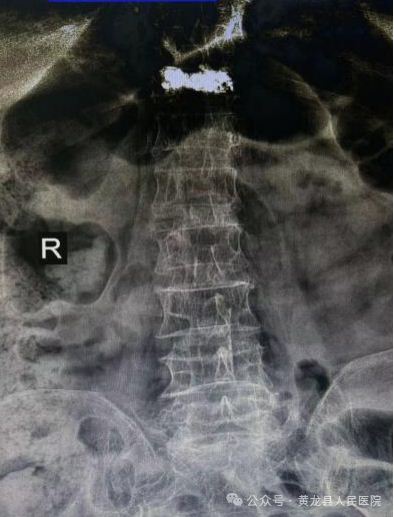

术前术后X线影像

患者女,88岁,因病理性骨质疏松导致胸腰背部疼痛,翻身、弯腰、下地活动严重受限。入院后行X线检查示:胸椎体压缩性骨折(胸11)。

术中最大限度保留了腰背肌肉的完整性,减少患者术后疼痛、手术出血和切口感染等手术并发症,同时大大缩短了患者康复时间。术后第1天,患者胸腰部疼痛显著缓解,不仅能自行完成床上翻身活动还可以下地活动,达到预期效果,术后第2天出院,恢复生活自理能力。患者及家属对手术治疗效果非常满意,向方继荣主任及外科全体医护人员多次表示感谢,出院后特送来锦旗一面再次表示感谢。